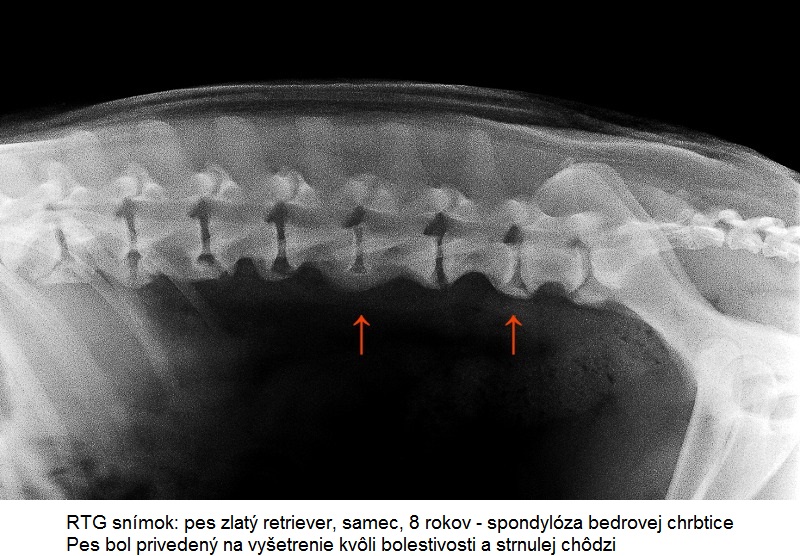

Spondylóza sa diagnostikuje z laterolaterálnej (pes leží na boku), prípadne ventrodorzálnej (pes leží na chrbáte) RTG projekcie. Myelografické vyšetrenie, CT alebo magnetická rezonancia pomôže odhaliť prípadnú kompresiu miechy. Spondylóza môže byť lokalizovaná v priebehu celej hrudnej (Th) a bedrovej chrbtice (L), až po oblasť posledného bedrového a prvého krížového stavca (S). Pričom často sa vyskytuje práve v oblasti prechodu jedného úseku chrbtice v nasledujúci (TH-L, L-S).

Jedná sa o progresívne ochorenie. Veľmi často je diagnostikovaná ako vedľajší nález pri RTG snímkoch zhotovených z iných dôvodov, keďže mnoho postihnutých jedincov ostáva asymptomatických po dlhšiu dobu. Klinicky sa spravidla prejaví až pri strednom a vyššom stupni ochorenia. Nástup klinických príznakov ovplyvňuje viacero faktorov ako plemenná príslušnosť, vek, hmotnosť a záťaž psa. Najčastejšie sa spondylóza prejaví u psov v strednom a vyššom veku, kedy už ani majiteľ neočakáva také fyzické výkony ako u mladšieho psa. Preto môže byť nástup klinických príznakov spočiatku prehliadaný a pripisovaný pribúdajúcemu veku.